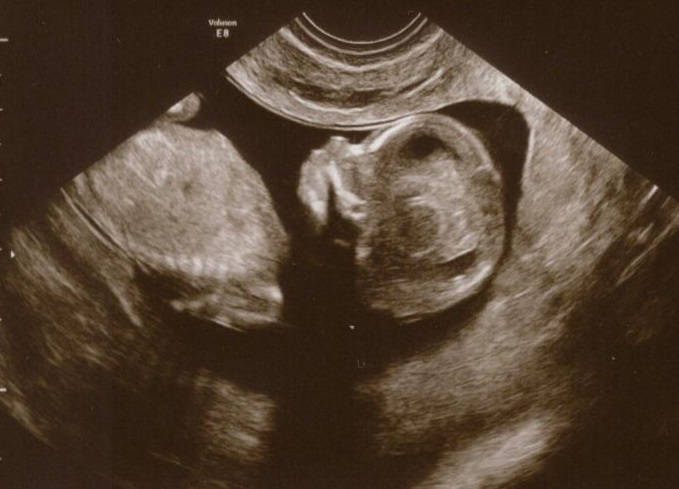

Zuzka a Marti, děkuji coby mluvčí za klubíčko za pochvalu. Je opravdu nádherné. Já měla předtím dva obrázky, ale z mnohem horšího ulrazvuku, to byly takové dvě bílé kuličky u sebe, jedna jako hlavička, druhá jak tělíčko. Tohle je už prostě miminko... úplně mě zamrazilo, když jsem si uvědomila, že jsem ještě v době, kdy některé ženy jdou na umělé přerušení... tohle je už opravdu človíček. Když vidíte jednotlivé prstíčky a orgány... úplně mě bylo klubíčka líto, když mě paní doktorka pořád tlačila na podbřišek a vrtala ve mě vaginální sondou, aby se klubíčko ve mně otočilo a ona mohla dokončit měření. Pořád se vrtělo, dokonce se chytalo za hlavičku, myslím, že nás po té půlhodině vrtání a šťouchání mělo opravdu dost. Ale zvládlo to na jedničku.

[321506] Mili, dnes jsme 13tt+0, fotka je ze čtvrtka, kdy jsme byly 12tt+4, termín mám aktuálně 1.12. Klubíčko měřilo od temene ke kostrči 6,8cm, stehenní kost 1,0cm, takže už je to dlouhán. Asi bude po mamince =)